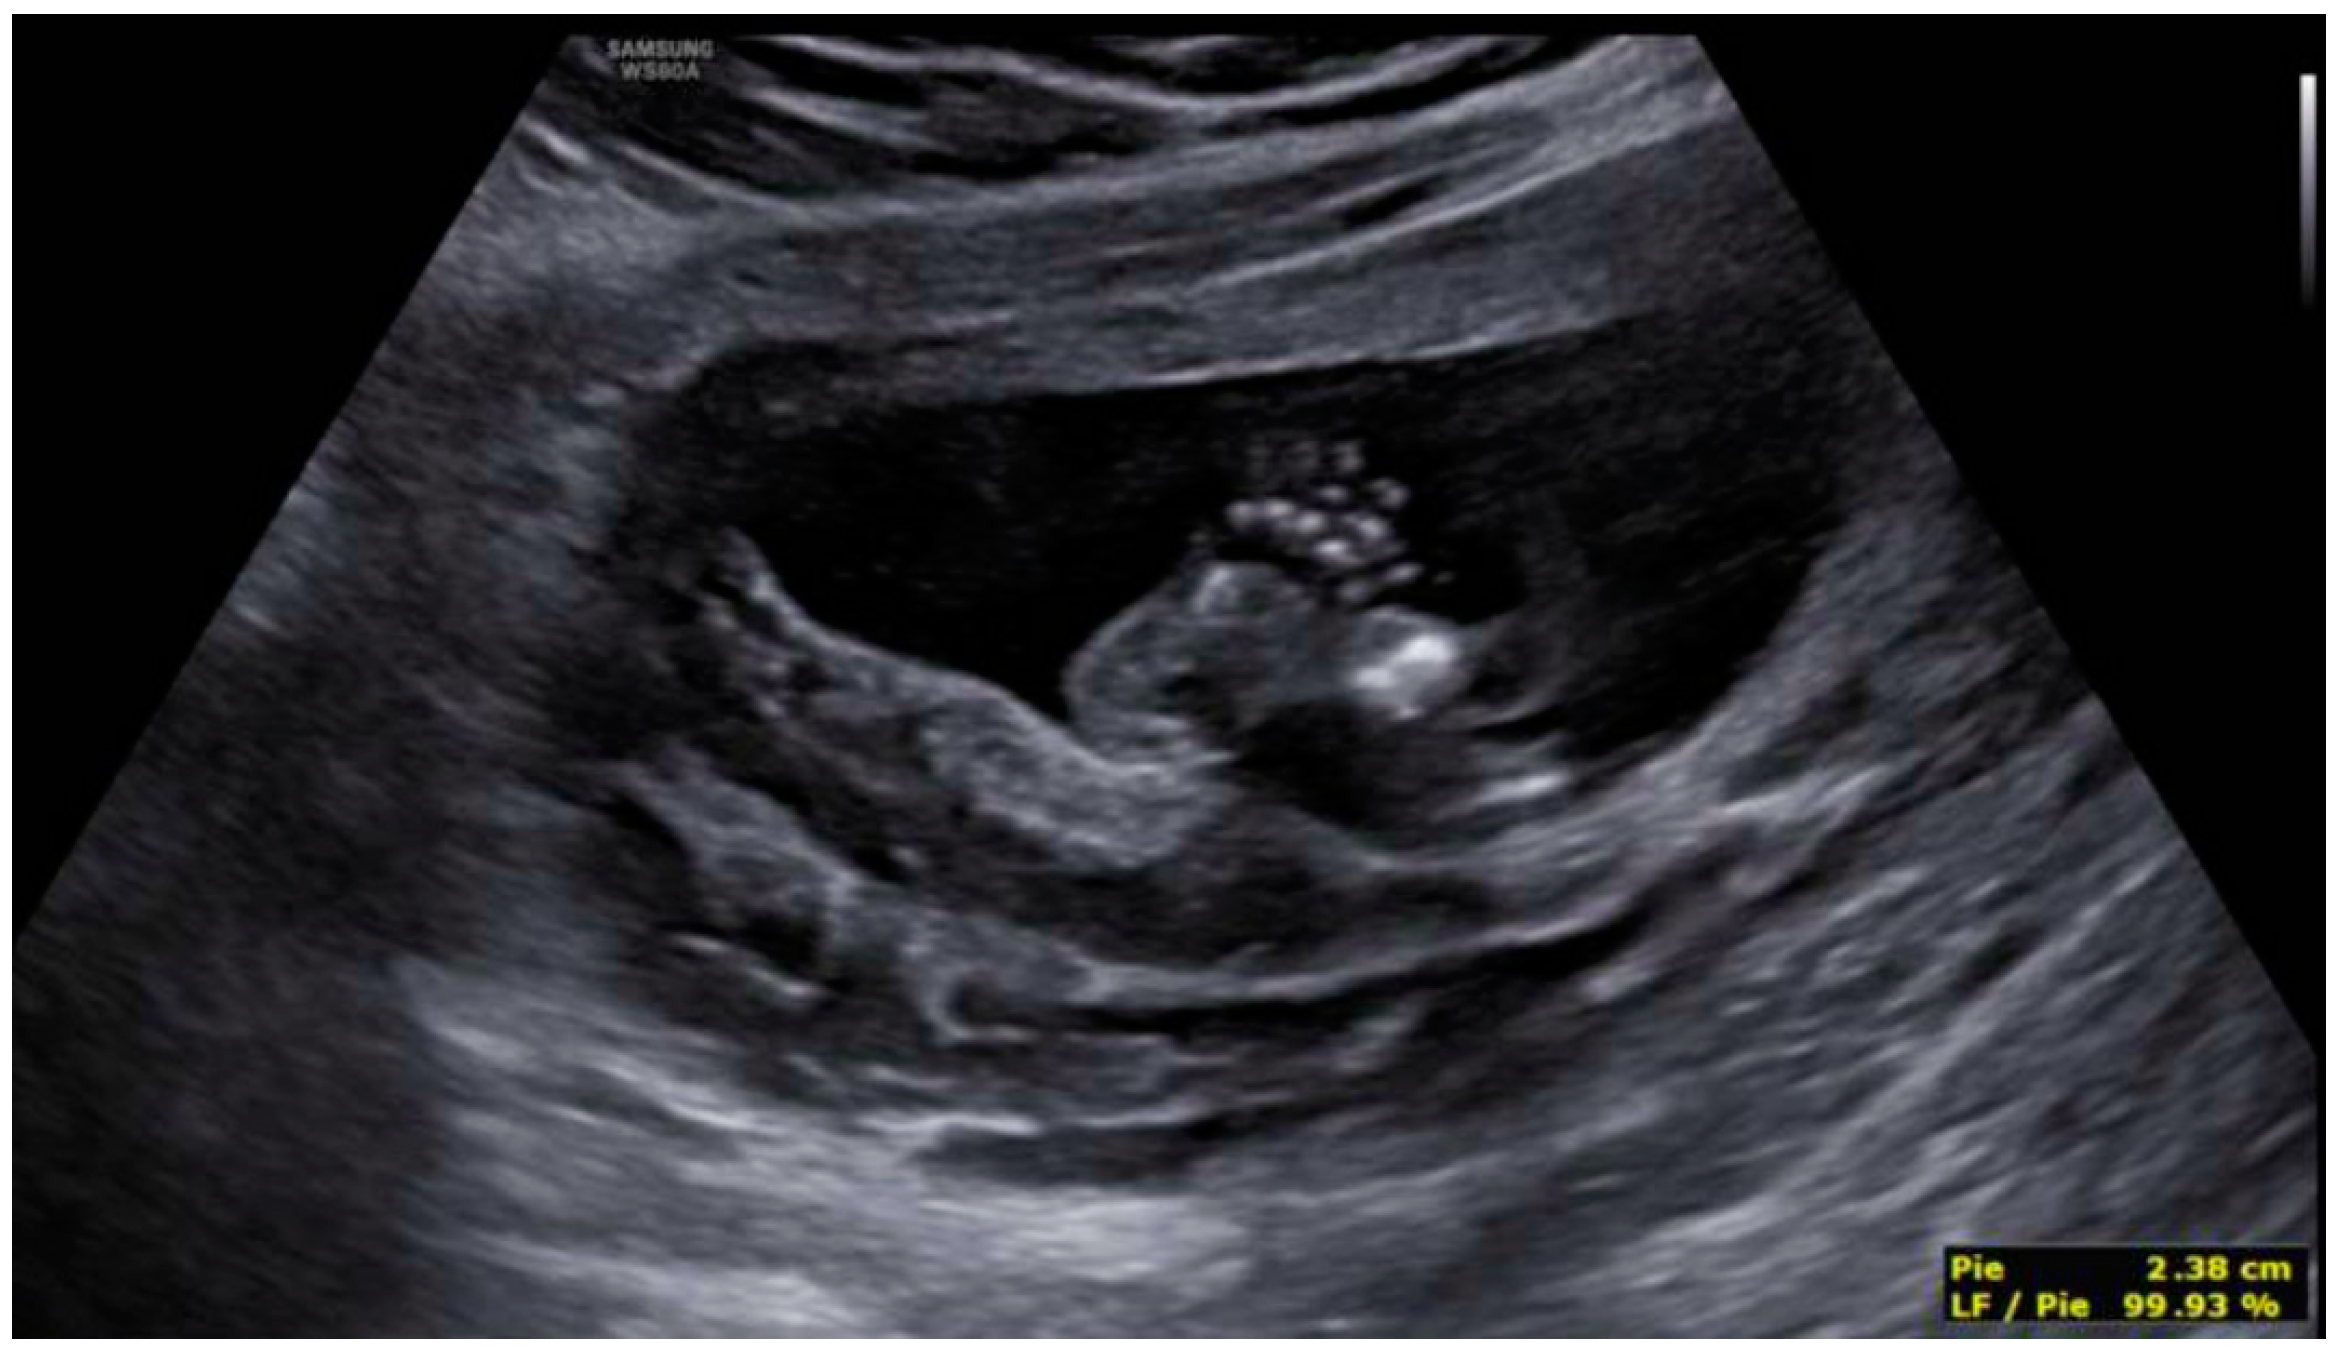

3. Results: Case Presentation